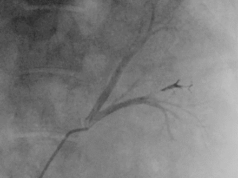

According to the company, Tembo is a bioresorbable embolization agent composed of irregularly shaped, dry-gelatine particles of a size range from 85 to 255µm. These particles are designed for the embolization of hypervascular tumours and blood vessels to occlude blood flow in the peripheral vasculature.